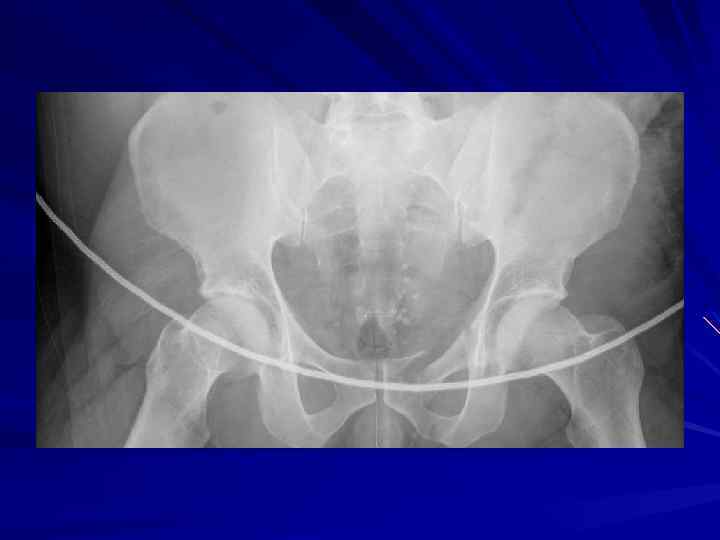

Пациент А. • Мужчина 53 года • ДТП • Жизненные параметры на месте происшествия (по записи бригады СМП): АД 114/80, ЧСС 130, ЧД 20, ШКГ 15

Приемный покой АД 74/48 | ЧСС 149 | ЧД 31 | Sp. O 2 88% | Темп. 37. 2°C Ø ШКГ 13 Ø Обширная рваная рана на затылке с продолжающимся кровотечением Ø Ушиб грудной клетки Ø Распространенная болезненность живота Ø Слабая пульсация на нижних конечностях Ø Обширная рваная рана на задней поверхности левого колена Ø Кровоподтеки и ссадины на обеих нижних конечностях

Операционная Ø Постоянная форма мерцательной артимии (варфарин? ) Ø Неэффективное самостоятельное дхание Интубация Ø Начат протокол массивной ИТТ Ø Катетеризация левой подключичной вены и лучевой артерии на правой руке Ø Рентген грудной клетки Ø Рентген таза

Операционная § Наложение фиксирующей повязки на таз § УЗИ ОБП – жидкость в брюшной полости § Диагностическая лапаротомия § § § Разрыв диафрагмы слева Разрывы печени и селезенки Множественные мезентериальные гематомы Обширная забрюшинная гематома Лимфорея справа